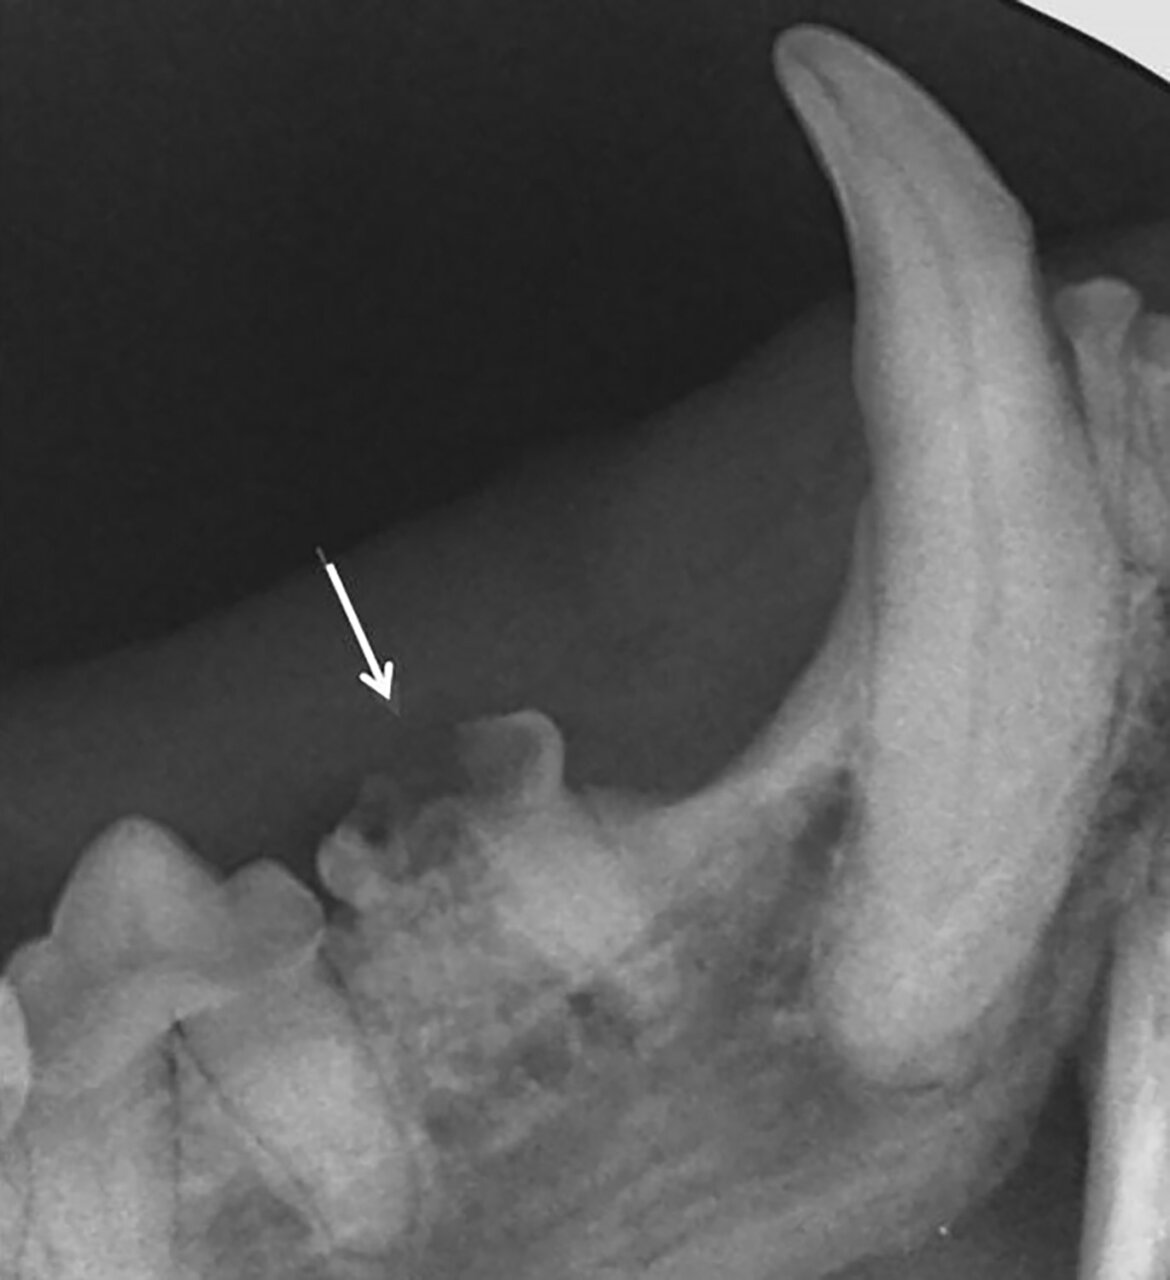

- Grado 2 (PD2): pérdida del soporte óseo menor al 25 % (imagen 7).

- Grado 3 (PD3): pérdida del soporte óseo de un 25-50 % (imagen 8).

- Grado 4 (PD4): pérdida del soporte óseo mayor de un 50 % (imagen 9).

Además de permitirnos evaluar el grado de enfermedad periodontal, también hace posible seleccionar el mejor tratamiento en función de su patología y las posibles complicaciones, como las fracturas mandibulares iatrogénicas en perros de talla pequeña con enfermedad periodontal PD4 (imágenes 10 y 11).